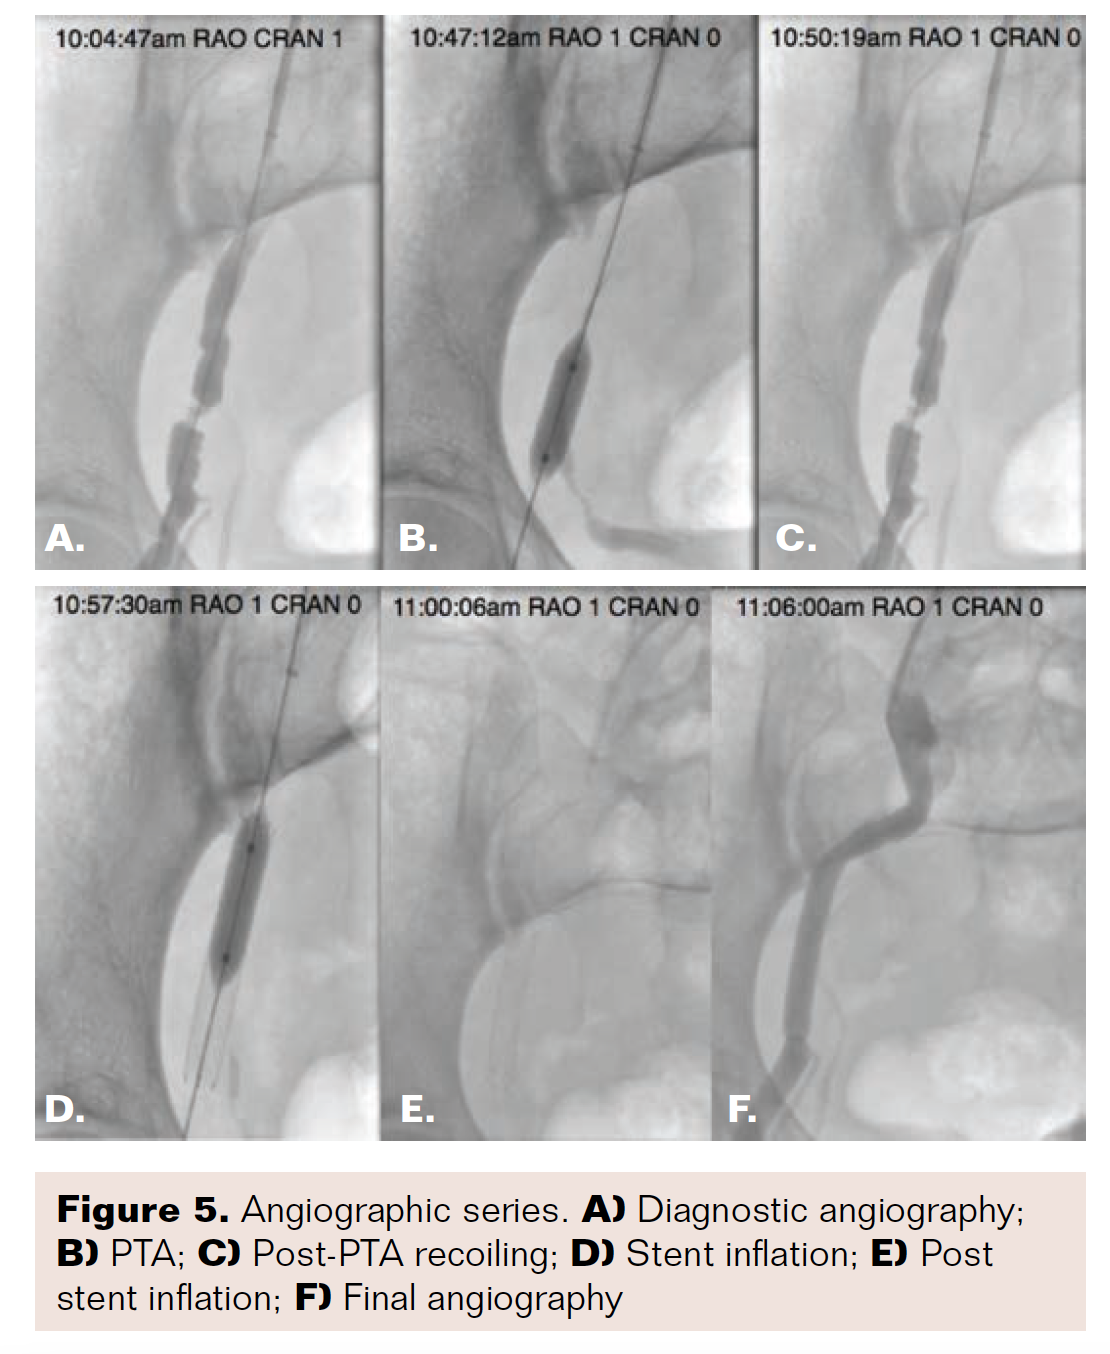

The patient was taken for selective abdominal aortography with bilateral runoff. After establishing access, a catheter was advanced to the distal superficial femoral artery and a significant pressure gradient (100 mm Hg) at the right external iliac artery was detected during pullback maneuver (Figure 4). A focused angiography revealed a focal high grade stenosis of 90% inside a vessel segment with a beaded appearance. A percutaneous transluminal angioplasty (PTA) was then performed on the right external iliac artery lesion with several inflations of a 7 mm × 2 mm balloon. Despite multiple inflations, there was consistent and substantial vessel recoiling. A 7 mm × 4 mmself-expanding nitinol S.M.A.R.T. stent (Cordis) was deployed in the area and then post-dilated with the 7 mm × 2 mm balloon in 2 inflations. There was an excellent angiographic result demonstrating complete resolution of obstructive disease (Figure 5).

Our report describes a patient with symptomatic, isolated FMD in the right external iliac artery who underwent a stent placement after multiple, unsuccessful angioplasty attempts due to recoiling of the vessel segment.